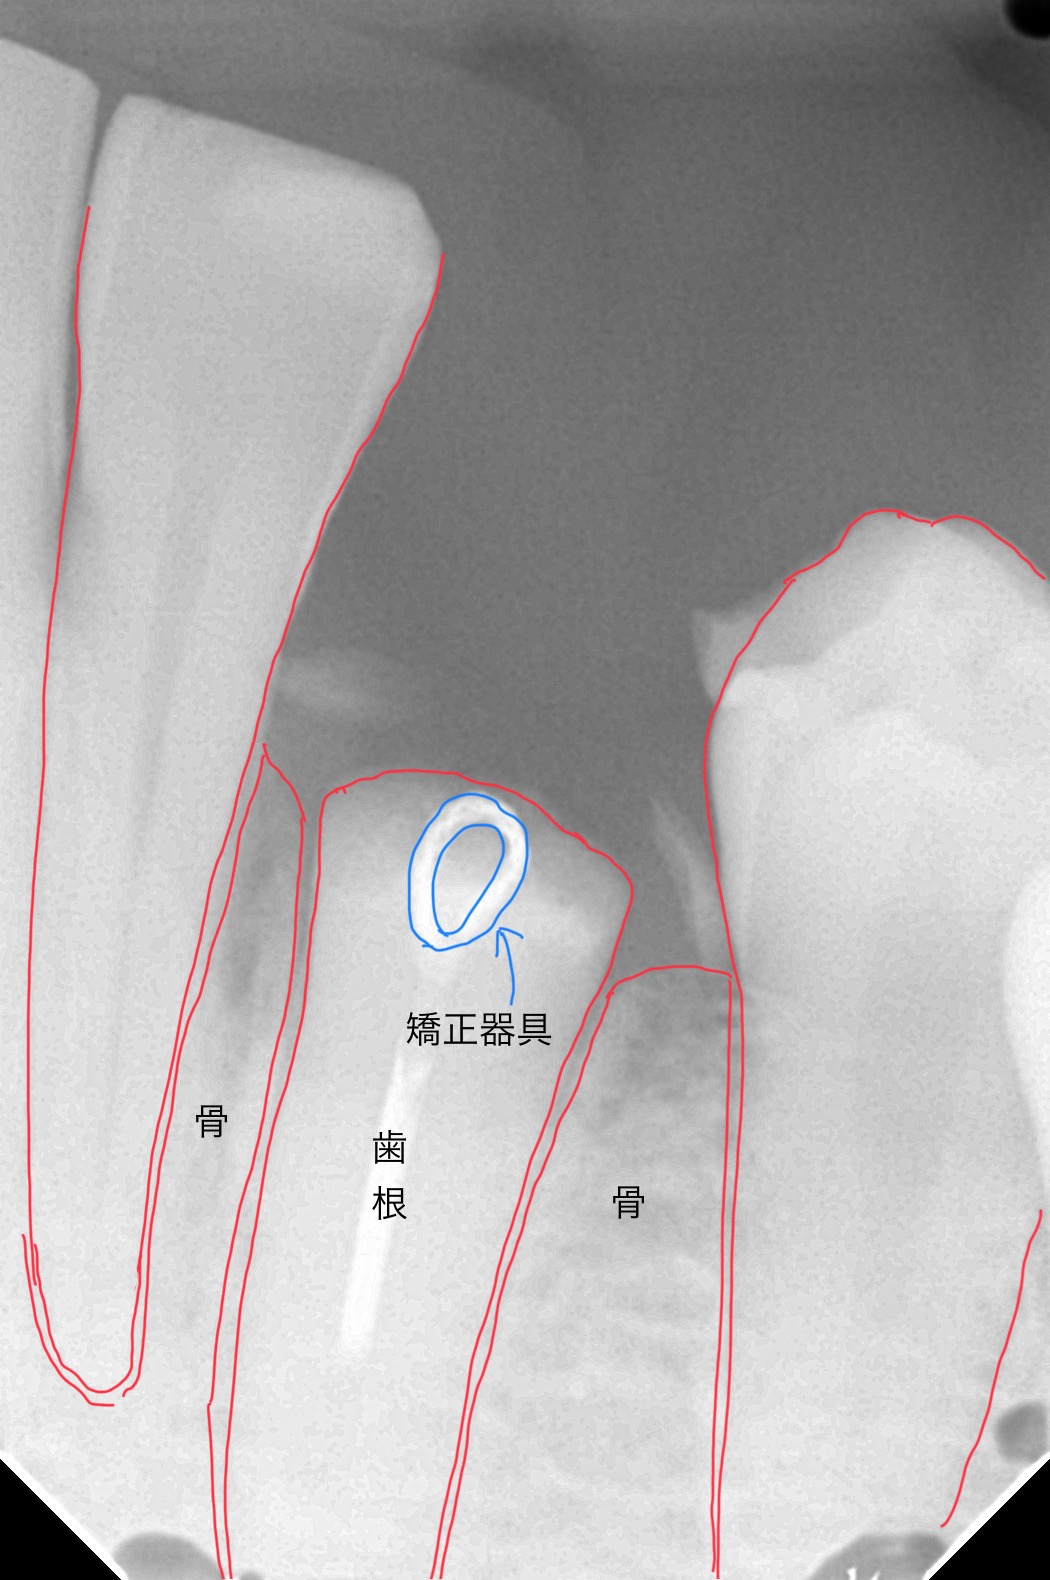

下のレントゲン写真は、歯根に輪っか状の器具(フック)を装着した状態です。レントゲンでは歯茎は映りませんが、歯根が骨のギリギリまで折れてしまっていることがわかります。ここからゴムやワイヤーの力を使って、少しずつ歯根を歯ぐきの外に引き出していきます。